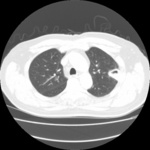

Sinal de "halo" em aspergilose pulmonar inicial

Do acervo do Dr. P. Chandrasekar; usado com permissão